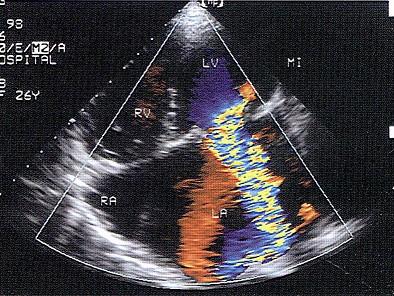

该病例二尖瓣返流面积与左房面积之比为37%,提示返流程度为?(?)A.轻微B.轻度C.中度D.重度E.无返流

问题 该病例二尖瓣返流面积与左房面积之比为37%,提示返流程度为?(?)

选项 A.轻微 B.轻度 C.中度 D.重度 E.无返流

答案 C